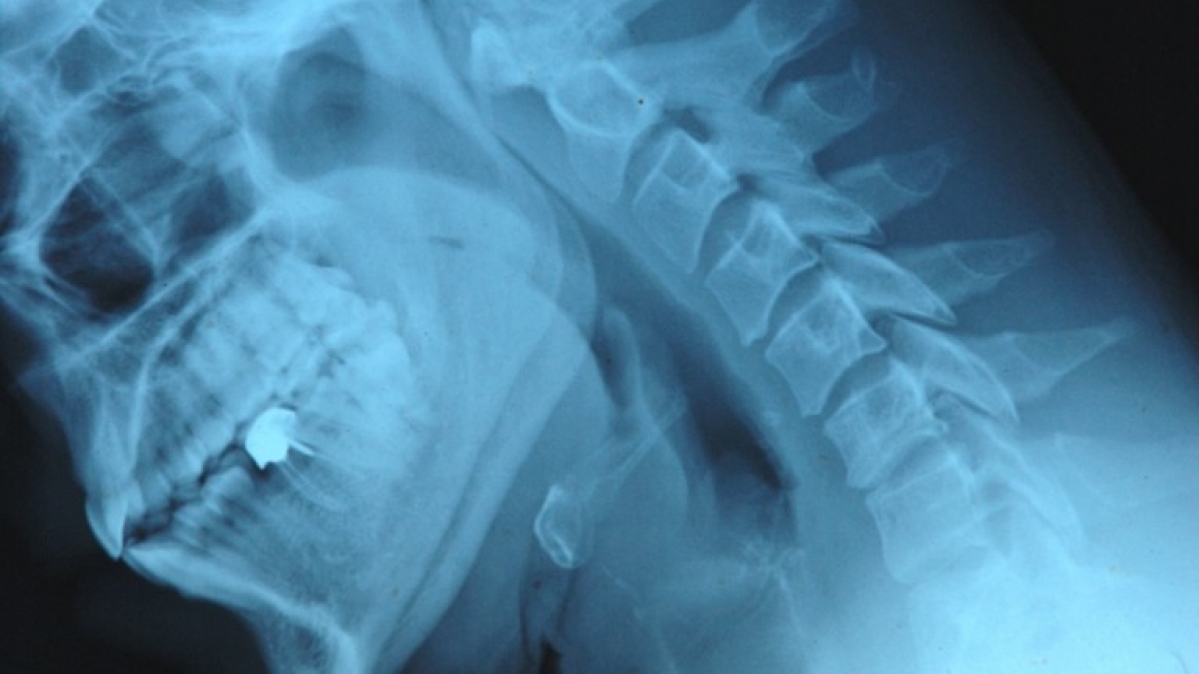

Meistens sehen wir sie nicht. Doch sie sind immer anwesend und beeinflussen unser Leben, unsere Gesundheit, unsere Freizeit. Die Bandbreite der Strahlungsarten ist riesig. Am liebsten ist es uns, wenn uns Sonnenstrahlen wärmen oder uns die Mikrowellen das Essen erhitzen. Trotz der Nebenwirkungen sind wir auch dankbar, dass Röntgenstrahlen schon lange einen Blick in unser Innerstes werfen können. Auf die aggressiven radioaktiven Verwandten würden wir eigentlich gerne verzichten. Und Sie? Wissen Sie, in welchen Bereichen Strahlung noch eine Rolle spielt? Viel Spaß beim Testen wünscht Ihnen die Redaktion!